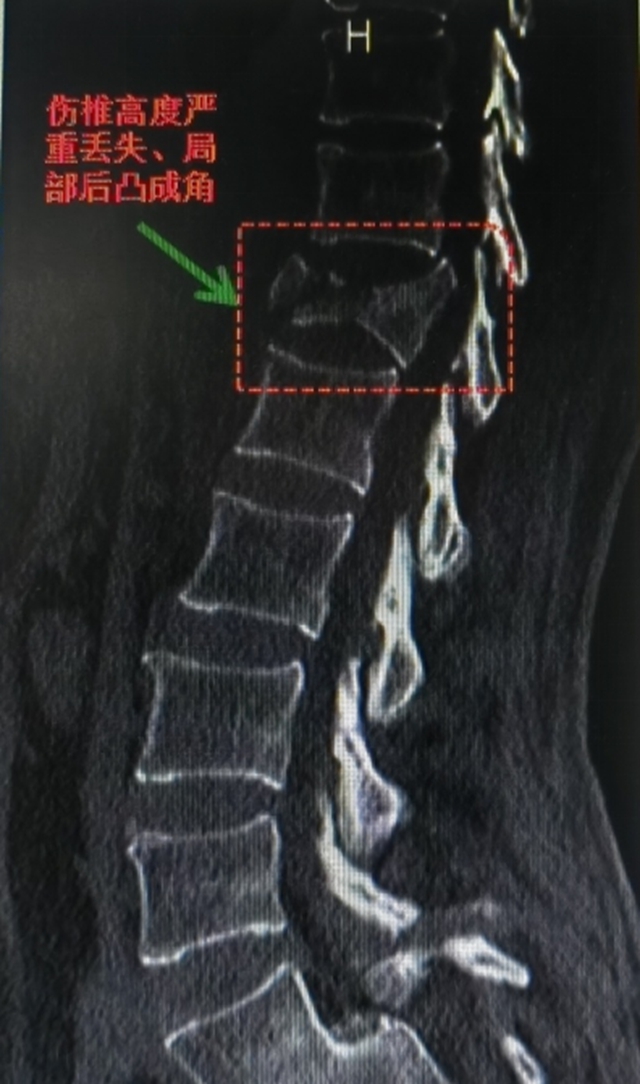

伤后,王女士立即被送往当地医院急诊进行救治,完善CT等相关检查后,发现其胸12椎体爆裂骨折,椎管占位明显,容积缩小50%以上,局部后凸成角。当地医院建议转至西南医科大学附属中医医院进行救治。

胸12椎体爆裂骨折:椎体如积木般碎裂,骨折块向后突入椎管,压迫脊髓;

脊髓严重受压:椎管容积缩小超50%,局部后凸畸形,脊髓功能濒临衰竭;